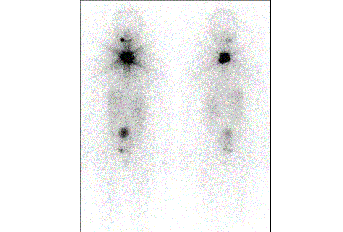

Two young doctors from the Portuguese Institute of Oncology of Lisbon reviewed the clinical files of more than 2,000 patients with Differentiated Thyroid Cancer and evaluated the risk of developing other primary cancer elsewhere. They concluded that total administered activities of Iodine-131 above 200mCi could increase the risk. But the administration of low activities was not associated with the risk of having other cancers. The Differentiated Thyroid Cancer is the most common cancer in endocrinology and it is believed its incidence will increase in the next years. Radioidine therapy has been performed for more than 70 years and it continues to be recommended after surgery, because it improves survival, helps in staging and in the follow-up of patients. The paper was published in June 2017 in a worldwide known American journal dedicated to thyroid diseases and it highlights the risk associated with high activities of Iodine-131 (which are used in specific clinical cases and in which clinicians need to weigh the risks and benefits).